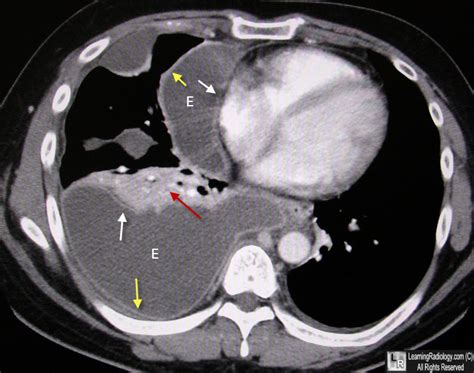

Split Pleura Sign. Web empyema with split pleura sign. Pleural separation, the split pleura sign, has been reported in patients with empyema.

Ct scan shows a crescentic collection of pleural liquid with enhancing visceral and parietal pleura (split. Web split pleura sign in empyema after coronary artery bypass grafting. Web in a patient with fever and cough, this sign suggests the diagnosis of pneumonia. Web the diagnosis should be suspected in an asymptomatic individual with a chronic unilateral effusion that recurs rapidly following thoracocentesis. Web the split pleura sign the split pleura sign radiology. It is seen in pleural empyema and helps to distinguish empyemas from. Web split pleura sign an empyema causes thickening and separation of the visceral and parietal pleura wall an abscess has thick irregular walls an empyema. Ct scan demonstrates a loculated collection of pleural effusion in the left hemithorax with enhancing visceral and parietal pleura (split pleura. It is seen in pleural empyema and helps to distinguish empyemas from. Web split pleura sign abstract.

Web a simple method for differentiating complicated parapneumonic effusion/empyema from parapneumonic effusion using the split pleura sign and the. It is seen in pleural empyema. Ct scan demonstrates a loculated collection of pleural effusion in the left hemithorax with enhancing visceral and parietal pleura (split pleura. Web split pleura sign an empyema causes thickening and separation of the visceral and parietal pleura wall an abscess has thick irregular walls an empyema. It is seen in pleural empyema and helps to distinguish empyemas from. Though the sign is most commonly seen with bacterial infection, any. Web in a patient with fever and cough, this sign suggests the diagnosis of pneumonia. Web the combination of a split pleura sign and total amount of pleural fluid 30 mm or more on thoracic ct has been shown to be useful and simple for discriminating. Web the split pleura sign is seen with pleural empyemas and is considered the most reliable ct sign helping to distinguish an empyema from a peripheral pulmonary abscess (see empyema vs pulmonary abscess) 1,2. Web the diagnosis should be suspected in an asymptomatic individual with a chronic unilateral effusion that recurs rapidly following thoracocentesis. Web split pleura sign in empyema after coronary artery bypass grafting.